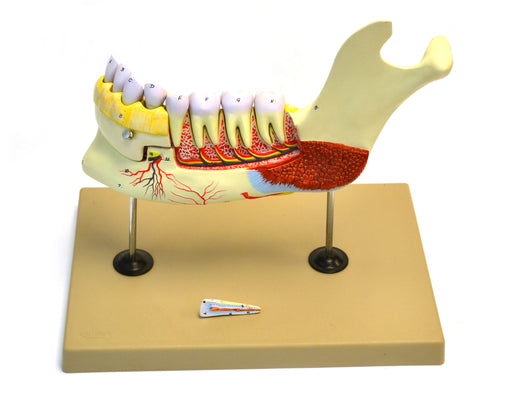

Lower Human Jaw Model - 5 times Life size

5 times life size Left Lower jaw Removable teeth This highly detailed model of the left side of a human lower jaw is enlarged 5 times life size. ...

View full detailsAM234AS -